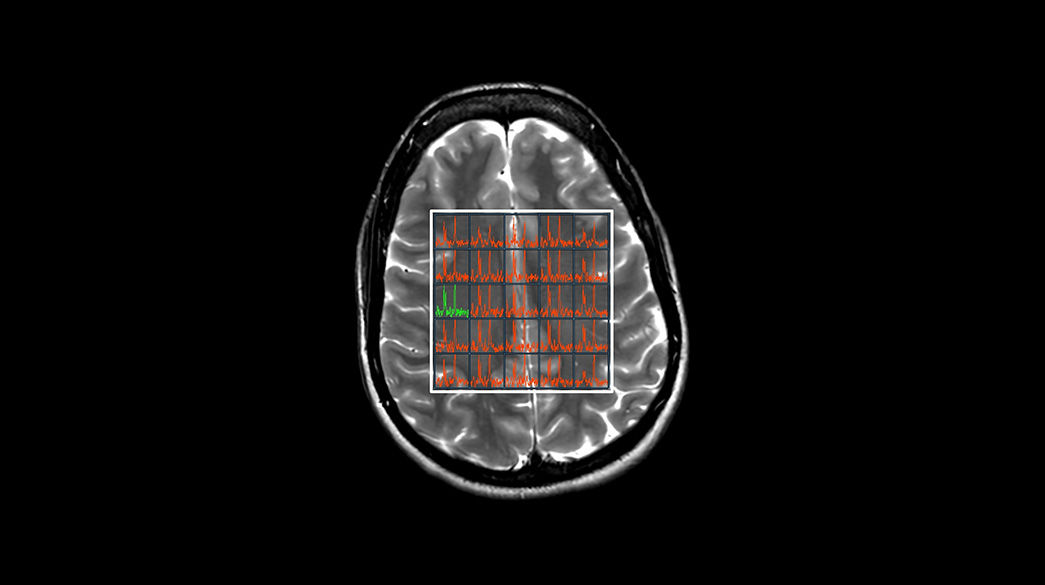

Oncology MR imaging techniques to capture anatomical and morphological data with robust tissue contrast, motion-insensitive and high temporal and spatial resolution for oncological assessment.

MR-Spectroscopy1040-x-585

Read case study ico-caret-right